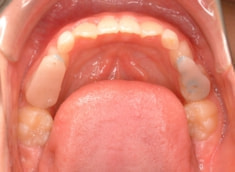

治療後(1年7ヶ月後)

フェイスマスクによる上顎の前方牽引の効果が認めらます。

治療前後の重ね合わせから、フェイスマスクの効果が認められます。